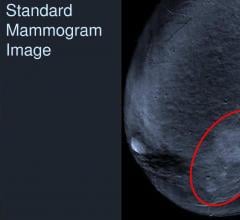

GE Healthcare, a business division of General Electric Company, announced it is joining with RadNet, a network of outpatient diagnostic imaging centers, to pilot its Best Pathways initiative, a breast cancer detection optimization model. GE Healthcare and RadNet will evaluate the clinical breast cancer detection process to quantify inefficient diagnostic patterns and identify optimal paths to lower cost and improve patient outcomes. This program will focus on subpopulations of women in which guidelines are lacking and substantial variability is observed in clinical practice.

August 3, 2012 — Rolling Oaks Radiology, a division of RadNet Inc., announced it now offers GE Healthcare SenoBright contrast-enhanced spectral mammography (CESM) at their Oxnard, Calif., location.